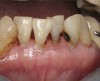

Fig 5. Use of 38% SDF to arrest coronal caries in primary teeth of a young child. The arrested carious lesion had a hard, blackened, and impermeable layer.

Figure 5